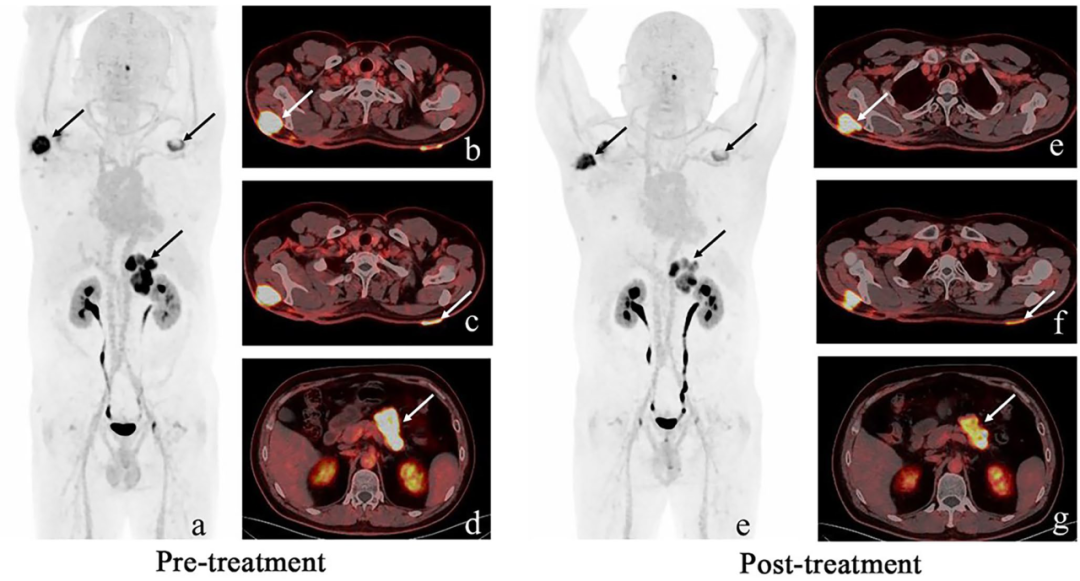

早在2024年10月,北京先通医药研发的1类放射性治疗药物“177Lu-XT117注射液”已率先获国家药品监督管理局药品审评中心(CDE)临床试验受理,本药物拟用于治疗经标准治疗失败或无标准治疗的FAP表达阳性晚期实体瘤患者。该药物获批受理后,先通医药积极联合医疗机构核医学科,有序推进相关临床研究的开展。

本表自制:Copyright © 夸克医药 All Rights Reserved.

2025年10月,177Lu-FAPI-XT的I期临床研究结果名为““Safety and efficacy of 177Lu-FAPI-XT radioligand therapy in patients with advanced sarcoma and other cancer entities: first-in-human, dose-escalation study”正式发表EJNMMI期刊。该研究聚焦于标准治疗无效的晚期实体瘤患者(其中78.6%为肉瘤),重点评估其安全性、剂量学与初步疗效。结果显示,疗法整体耐受性良好,未出现剂量限制性毒性或≥3级治疗相关不良事件,全身有效剂量为0.039±0.013 Sv/GBq。在疗效方面,35.7%的患者实现疾病稳定(SD),尤其在纤维源性肉瘤亚型中表现更为突出(SD率达50%),显示出良好的临床应用潜力。

图文源自:Eur J Nucl Med Mol Imaging. 2025 Oct 15.

尽管在11.1 GBq剂量水平未观察到剂量限制性毒性(DLT),但研究未继续推进剂量递增,推测可能出于以下考虑:红骨髓潜在辐射风险较高、同类FAP靶向药物的最高报告剂量为9.25 GBq,以及该剂量下未见疗效进一步提升。本研究整体疗效有限(未观察到部分缓解或完全缓解)还可能与以下因素有关:FAPI-XT117在肿瘤内滞留时间较短,导致辐射剂量累积不足;FAP主要表达于肿瘤基质细胞而非肿瘤细胞本身,限制了辐射对肿瘤细胞的直接杀伤效果;部分肉瘤亚型侵袭性强、辐射敏感性低,以及晚期患者肿瘤负荷较大。为提升疗效,采用α核素225Ac标记的新一代药物[225Ac]Ac-FAPI-XT(XT117)已进入临床研究,并开始患者招募,相关信息可搜索NCT07135128做进一步了解。